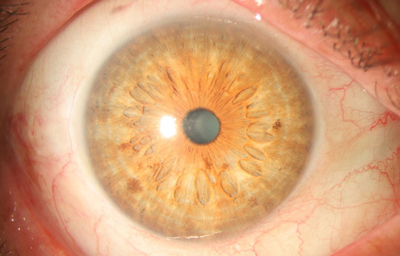

Policória: significa la presencia de varias pupilas en un Iris, es un hallazgo extremadamente raro, aclarando que el término se debe emplear solamente, para los casos en que la apertura esta rodeada por un esfínter completo; si no, es una policoria falsa.

Policoria falsa en midriasis OI: sinequia en el borde pupilar temporal con banda fibrosa 3 a 4; se ve el collarete y el esfínter periféricos a la pequeña pupila, lineas de tracción superiores e inferiores hacia el puente que separa las 2 aperturas de la 1 a las 5 - dentro de apertura pequeña, parece existir un remanente de membrana pupilar.

Archivo Fotográfico Dr. Carmen Barraquer. 1983